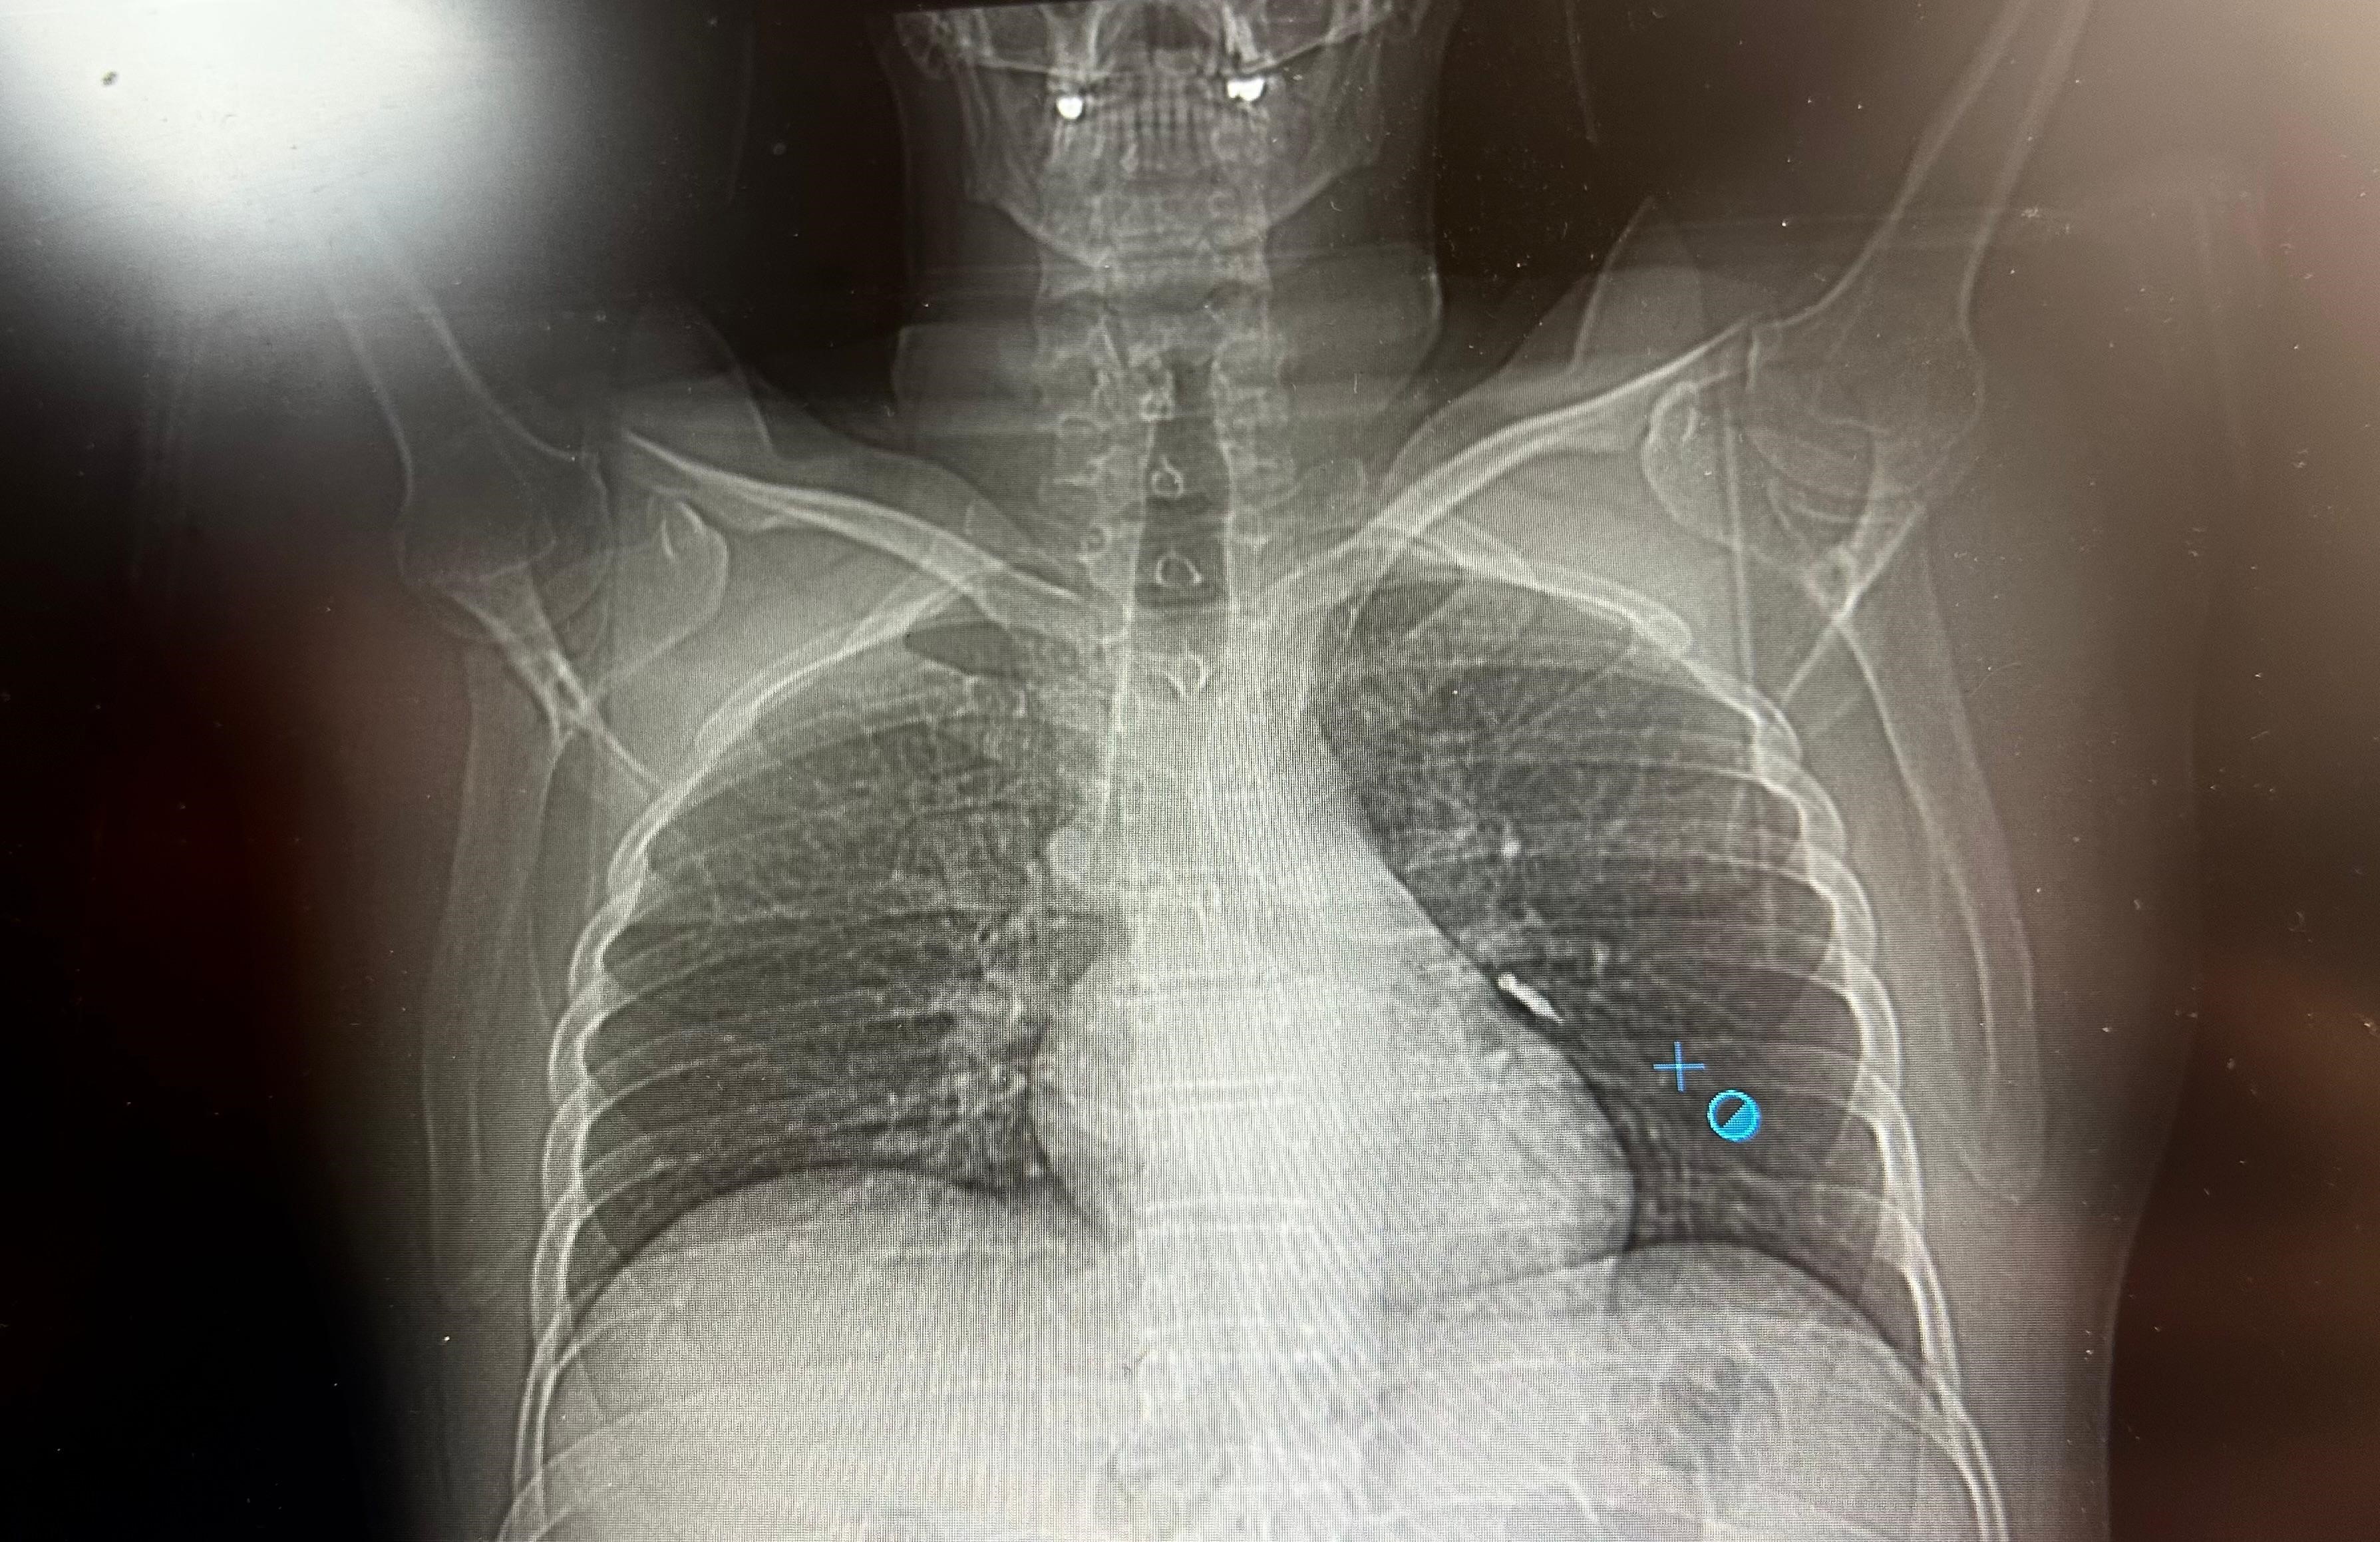

Göğüs Cerrahisi uzmanları Dr. Sadullah Aksoy ve Dr. Beniz İrem Ersoy Şığva tarafından hastaya bronkoskopi işlemi uygulandı. Sol akciğerin üst lobunda saplanmış şekilde tespit edilen vida, vidalı yapısı ve bulunduğu konum nedeniyle güçlükle yerinden oynatılabildi. Yapılan uzun ve titiz müdahale sonrası vida yerinden çıkarılamasa da hasta bir süre sonra geçirdiği öksürükle birlikte implant vidasını midesine gönderdi. Vida, daha sonra doğal yollarla vücuttan atıldı.

Konuya ilişkin konuşan Göğüs Cerrahi Op. Dr. Sadullah Aksoy, bir diş merkezinde diş tedavisi sırasında hastanın çenesine yerleştirilen implantın vida kısmının işlem esnasında yanlışlıkla aspire edildiğini belirtti. İlk olarak hastanenin ek hizmet binasında çekilen tomografi sonucunda, vidanın sol akciğerin hava yollarının yaklaşık dördüncü dalına kadar ilerlediği tespit edildiğini ifade eden Op. Dr. Aksoy, "Geçtiğimiz cumartesi günü öğle saatlerinde tarafımıza ulaşıldığında, hastanın Van Eğitim ve Araştırma Hastanesi'ne yönlendirilmesini istedik. Burada acil bronkoskopi planı yapılarak hasta kabul edildi. Hasta geldiğinde genel durumu iyiydi; solunumunu tamamen engelleyen bir bronş tıkanıklığı söz konusu değildi. Aynı gün hastamızı hazırladık. Bronkoskopi sırasında, implant vidasının sol üst lobun anterior segment bronşuna saplanmış pozisyonda olduğunu gördük. Üroloji bölümünde taş çıkarma işlemlerinde kullanılan cihazla müdahale ettik. İlk denemede implant tamamen çıkarılamadı ancak yerinden oynatılabildi. Bunun üzerine bir süre bekleyip hastayı yeniden bronkoskopi için hazırlamaya başladık. İşlem yaklaşık 3,5-4 saat sürdü ve saat 18.30 civarında hasta işlemden çıkarıldı" dedi.

Daha sonra hasta için yeniden bronkoskopi planladıklarını ancak bu süreçte hasta şiddetli bir öksürük geçirdiğini anlatan Aksoy, "Şiddetli öksürük sonrası yapılan kontrol akciğer filminde implant vidası görünmedi. Bunun üzerine toraks ve batın BT (bilgisayarlı tomografi) görüntülemesi istedik. Sonuçlarda implantın akciğerden çıktığı ve vücutta herhangi bir yerde bulunmadığı tespit edildi" diye konuştu.